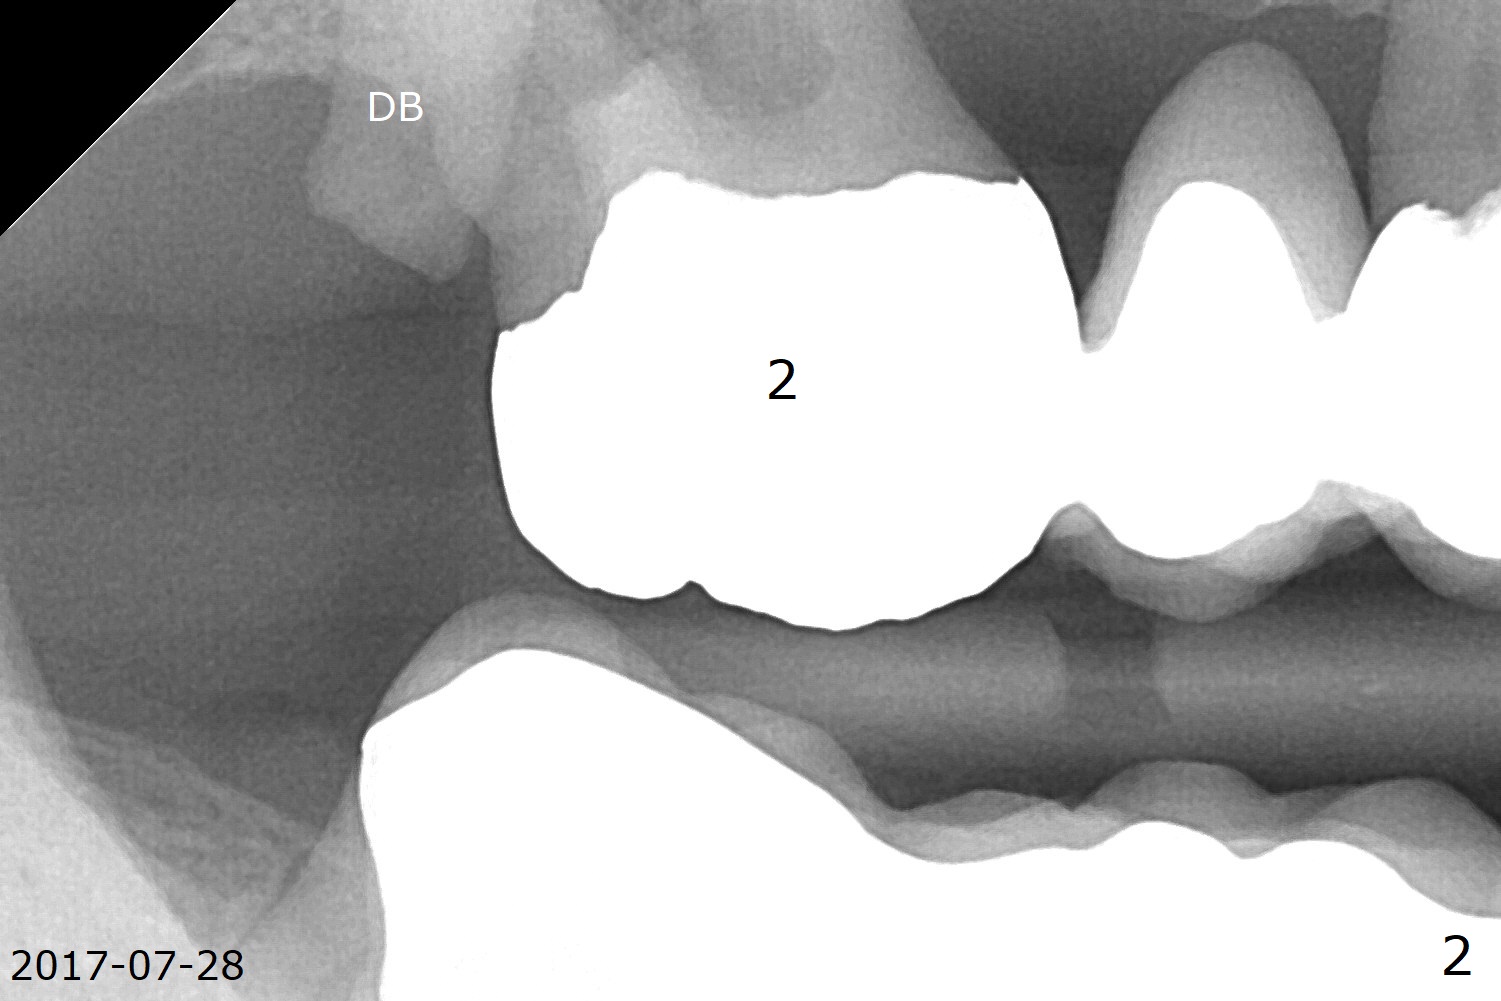

A 66-year-old man has asymptomatic distobuccal (DB) root fracture for ~ 3 years (Fig.1 (>) 2). After #14 implant with limited (M) ortho and 27 and 31 RCT (Fig.3,4), he agrees to have #2 and 3 implants. The tooth #2 has palatal fistula and is tender. Take preop photos. CT should reveal extensive bone loss. Use PRF/sticky bone or GEM21S (if venopuncture is hard) for repair. Save bone from #3 osteotomy for #2 bone graft. Use a special suction with trap after granulation tissue removal.